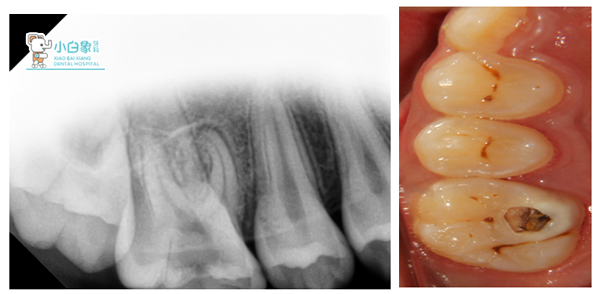

魏** 男 12岁

主诉:右上后牙疼痛半年余。

现病史:半年前右上后牙嵌塞食物,偶有疼痛,近一周加重,影响睡眠,要求检查。

检查:颌面部查未见异常,口内查:16近中舌尖龋坏达髓腔,探诊疼痛,温度测试疼痛,叩(++),余未见明显异常,口腔卫生尚可。

X线:16低密度影像达髓腔,近中根尖见低密度影像。

诊断:16慢性根尖周炎急性发作